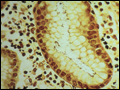

| Figure 293-14 Chronic gastritis and H. pylori organisms. Steiner silver stain of superficial gastric mucosa, showing abundant darkly stained microorganisms layered over the apical portion of the surface epithelium. Note that there is no tissue invasion. | |